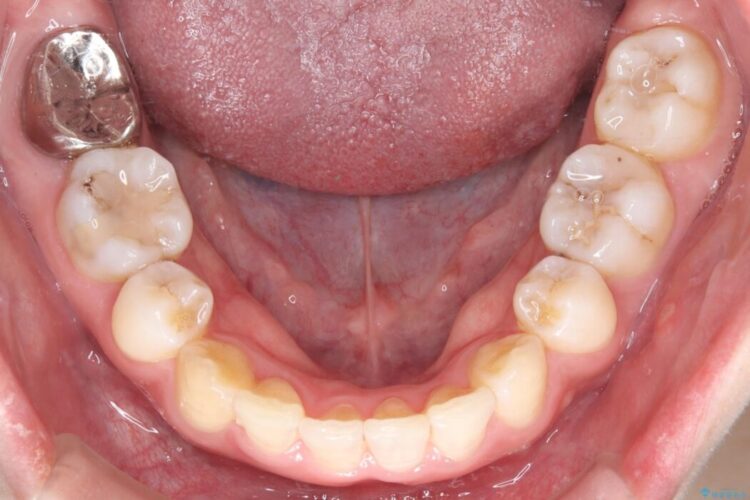

治療後について

長年の悩みだった重度の乱れが解消され、口元の突出感もすっきり改善。見た目も機能も安定した、理想的な歯並びを獲得していただけました。